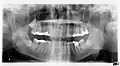

На панорамной рентгенограмме зубов видна зубная киста (отмечена стрелкой)